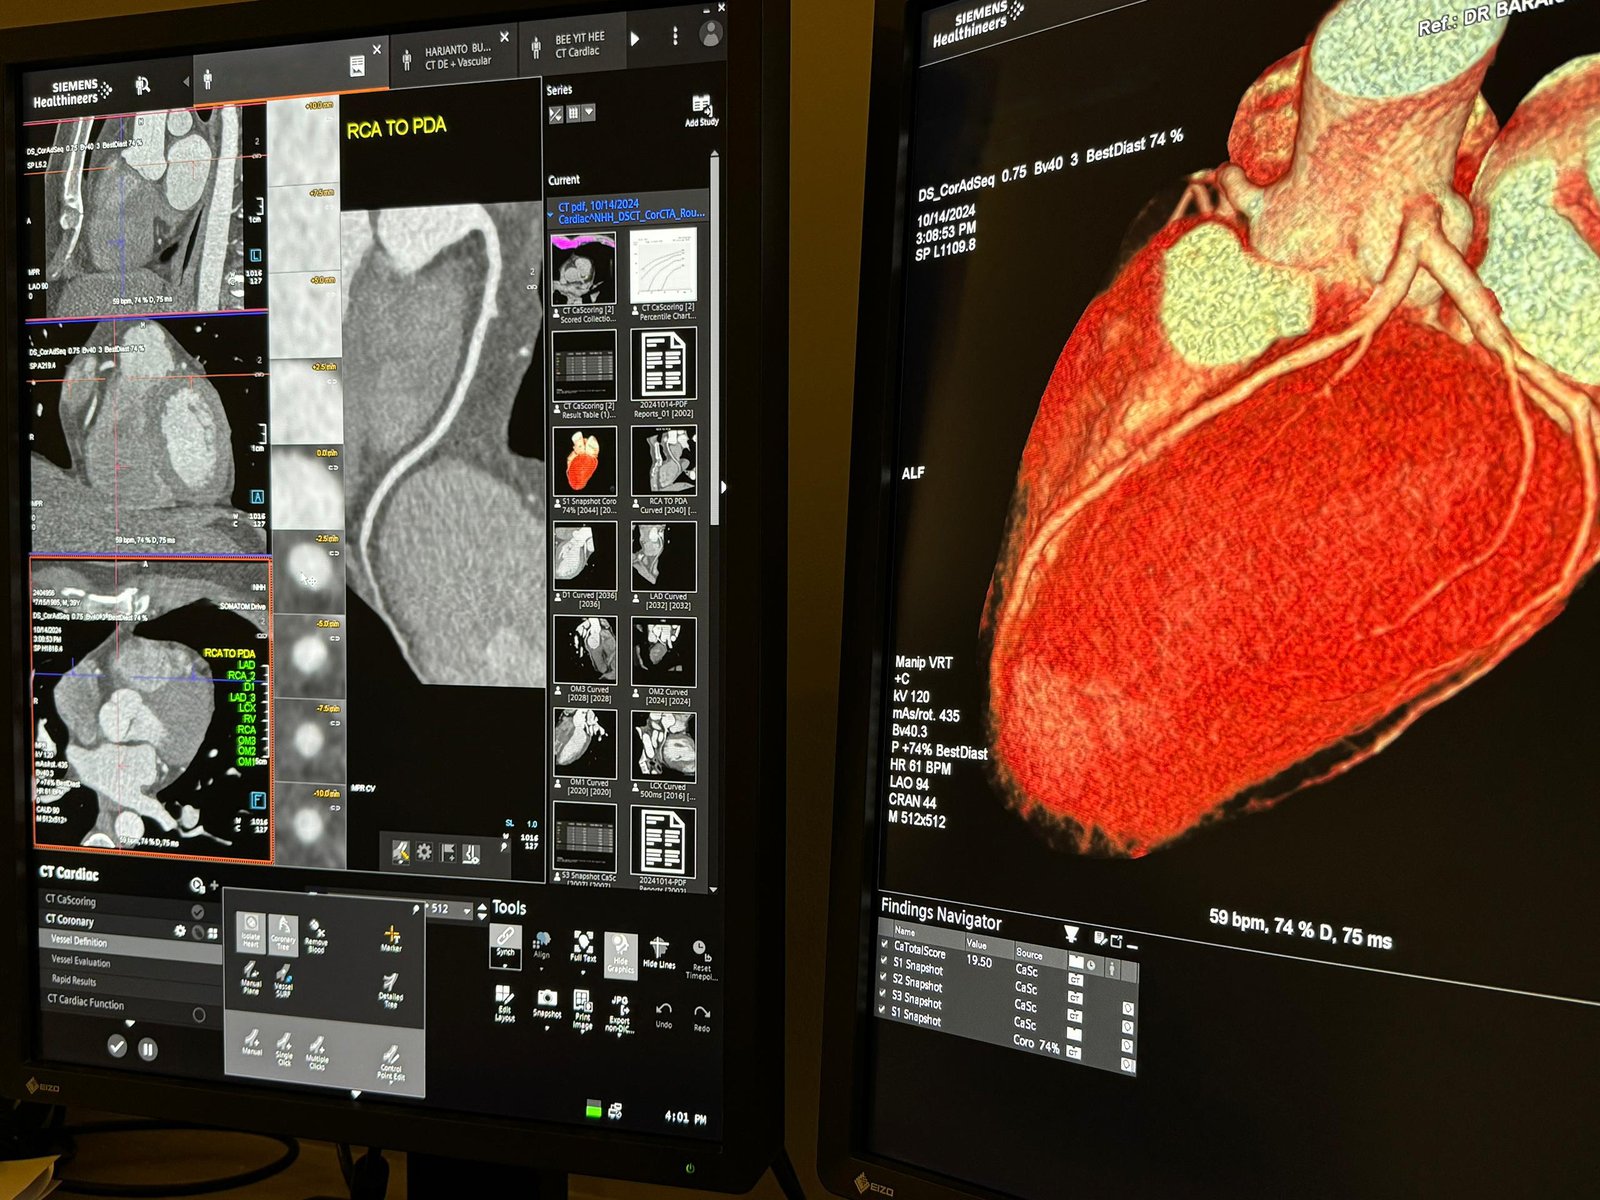

A Cardiac Computed Tomography (CT) scan is a non-invasive imaging technique that uses X-rays and computer technology to create detailed cross-sectional images of the heart and surrounding blood vessels. This advanced method allows doctors to get a closer look at the heart’s structure and function without the need for surgery.

Cardiac CT scans are frequently used to assess coronary arteries, diagnose heart diseases, and evaluate the effectiveness of treatments and interventions. With high-resolution 3D images, healthcare providers can detect abnormalities that might not show up in regular X-rays, making it an invaluable tool in cardiovascular care.

- Coronary Calcium Scoring: A cardiac CT scan can also measure the amount of calcium in the coronary arteries, helping to predict the risk of future heart disease.